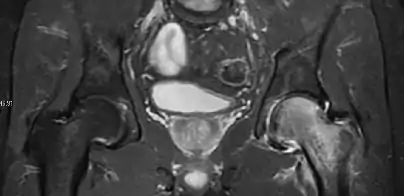

Figure 8:

X-ray of a patient with transient osteoporosis of the left hip showing osteoporosis.[1]

Coronal stir imaging in transient osteoporosis, showing diffuse edema.[1]

Scintigraphy (A), sagittal T1 (B), and coronal PD fat sat of a patient with a subchondral fracture of the femoral head with convex shape to the articular surface.[1]

Coronal T1 of a patient with avascular necrosis of the femoral head.[1]